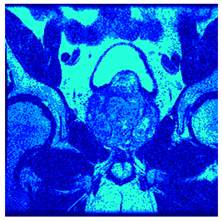

In this subsection, we will discuss the experiment designed to evaluate the performance of EO with cross-entropy for the segmentation of prostate MRI images. To this end, we use a group of reference images formed by a set of six prostate MRI images; see Figure 4. All the images from the group were extracted from the Ferenc Jolesz National Center for Image-Guided Therapy, Harvard Medical School, or Brigham Health Hospital datasets with no additional preprocessing [50]. Prostate MRI images are primarily used for disease diagnosis or to establish treatment for prostate-related diseases such as prostatitis, benign prostatic hyperplasia (BPH), and prostate cancer, among other diseases or medical conditions. In the context of this article, the images were used to test the efficiency of the equilibrium optimizing algorithm and compare it with the other six chosen algorithms. The segmentation of MRIs is carried out over four different thresholds levels: = 3, 4, 5, and 8. Due to the nature of the images, there was a limited number of different tissues in the images; thus, there was no point in evaluating a larger number of .

Figure 4.

Eleven transaxial-cut prostate MRI images. This figure presents a set of eleven transaxial-cut magnetic resonance (MR) images of the prostate. These images serve as the input dataset for evaluating the segmentation performance of the proposed algorithm.